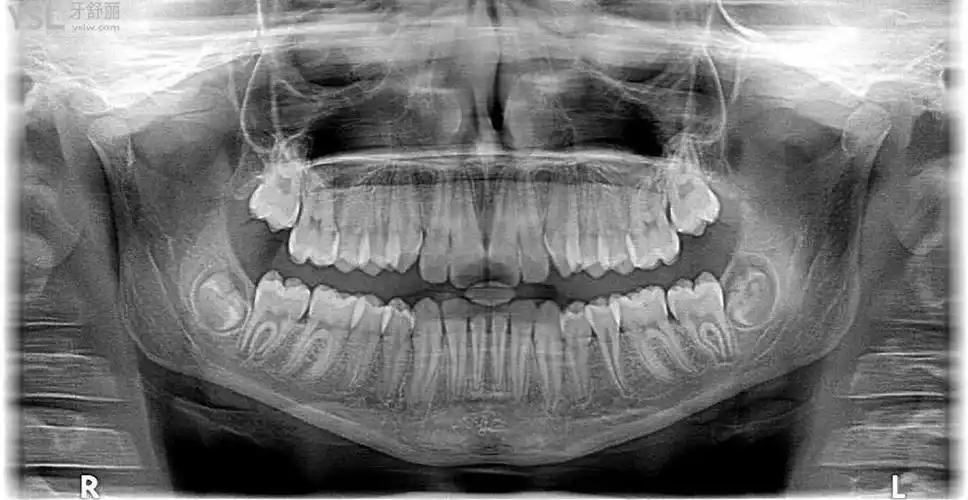

口腔ct片